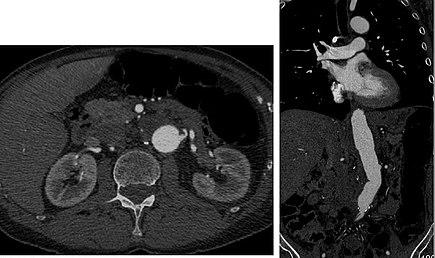

Axial and coronal view of abdominal CT angiography

Aorta and great arteries

CTA can be used in the chest and abdomen to identify aneurysms in the aorta or other major blood vessels. These areas of weakened blood vessel walls that bulge out can life-threatening if they rupture. CTA is the test of choice when assessing aneurysm before and after endovascular stenting due to the ability to detect calcium within the wall.[2] Another positive of CTA in abdominal aortic aneurysm assessment is it allows for better estimation of blood vessel dilation and can better detect blood clots as compared to standard angiography.[3]

CTA is used also to identify arterial dissection, including aortic dissection in the aorta or its major branches. Arterial dissection is when the layers of the artery wall peel away from each other; this causes pain and can be life-threatening. CTA is a quick and non-invasive method of identifying dissections and can show the extent of the disease and if there is leakage.[3]